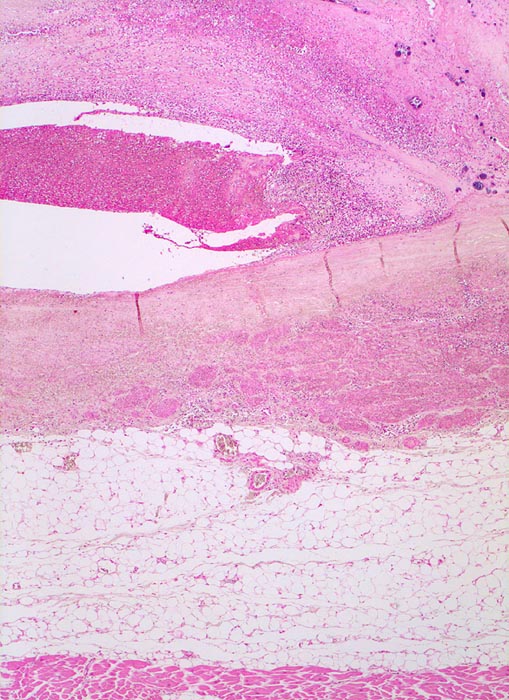

Endocarditis ulcero-polyposa der Aortenklappe

Aortenklappe

Herzklappe unmittelbar distal des Ansatzrandes vollständig zerstört. Klappenskelett kaum mehr zu erkennen. Polypöse Vegetation aus Fibrin und Granulozyten durchsetzt von Bakterien ersetzt die zerstörte Klappe.

Akut einsetzendes Krankheitsbild mit Fieber, Schüttelfrost, Müdigkeit und Dyspnoe. Blutkulturen wiederholt positiv für Staphylokokkus aureus. Keine Klappenvorschädigung bekannt.

Histologie

25